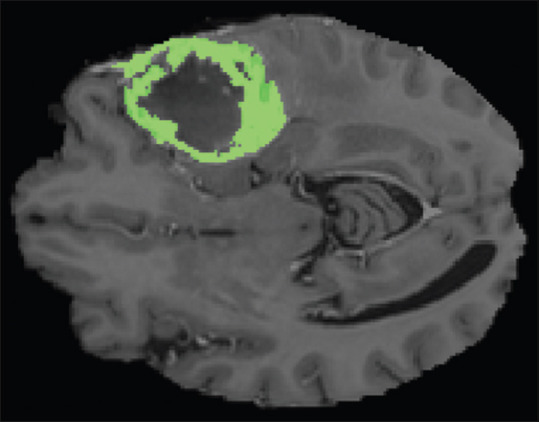

准确可靠的脑肿瘤分割对肿瘤的诊断和治疗计划具有重要意义。目前脑肿瘤分割的非监督方法很少。本文提出了一种新的基于图着色的无监督脑肿瘤分割方法。在本研究中,使用图形着色方法对脑肿瘤进行分割。为此,将脑图像的每个像素作为图的一个节点,将几个像素的亮度差作为边缘。该方法适用于低分级和高分级患者的t1增强磁共振图像。由于图形着色需要刚性图,因此必须使用阈值将边缘划分为存在或不存在的边缘。该阈值的大小直接影响图像分割的精度,因此选择最优阈值至关重要。该阈值的最优值为像素间亮度差最大值的0.42,使相关精度达到83.62%。结果表明,图着色方法是一种可靠的无监督脑肿瘤分割方法。该方法作为一种无监督方法,与神经网络和神经模糊网络相比,具有更好的准确率。然而,作为一个限制,这种方法的准确性依赖于边缘的阈值。

It is important to have an accurate and reliable brain tumor segmentation for cancer diagnosis and treatment planning. There are few unsupervised approaches for brain tumor segmentation. In this paper, a new unsupervised approach based on graph coloring for brain tumor segmentation is introduced. In this study, a graph coloring approach is used for brain tumor segmentation. For this aim, each pixel of brain image assumed as a node of graph and difference between brightness of a couple of pixels considered as edge. This method was applied on T1-enhanced magnetic resonance images of low-grade and high-grade patients. Since a rigid graph was needed for graph coloring, edges must be divided into existing or nonexisting edge using a threshold. The value of this threshold has affected the accuracy of image segmentation, so the choice of the optimal threshold was important. The optimal value for this threshold was 0.42 of maximum value of difference of brightness between pixels that caused the 83.62% of correlation accuracy. The results showed that graph coloring approach can be a reliable unsupervised approach for brain tumor segmentation. This approach, as an unsupervised approach, shows better accuracy in comparison with neural networks and neuro-fuzzy networks. However, as a limitation, the accuracy of this approach is dependent on the threshold of edges.